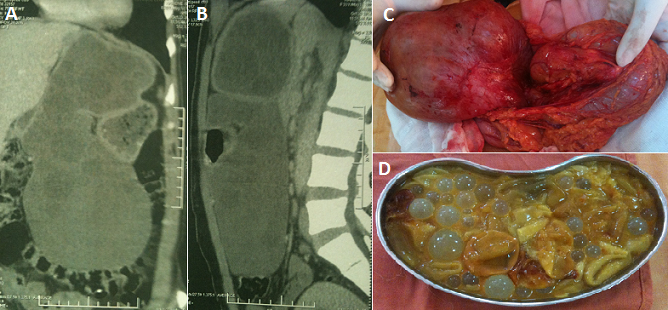

Le kyste hydatique du foie: à propos d’un cas inhabituel

Le kyste hydatique du foie (KHF) est un parasite de développement lent qui génère des lésions anatomopathologiques variées, responsables de tableaux cliniques divers et polymorphes. Le but du traitement est d’éliminer le parasite, et de régler le problème de la cavité résiduelle et des éventuelles complications associées.